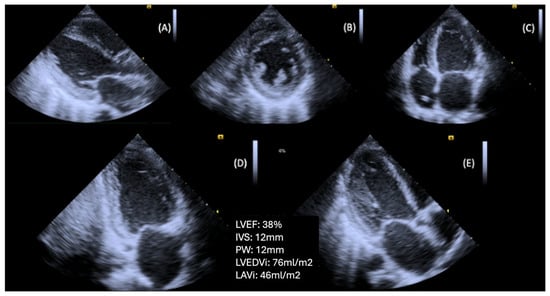

Diastolic dysfunction in individuals with DM is associated with a worse prognosis, as these patients face a higher risk of developing HF, compared to their counterparts without diastolic dysfunction [45]. Optimizing DM treatment and reducing HbA1c levels may lead to improvements in diastolic dysfunction, potentially delaying the progression to HF [56] (Figure 1).

Prolonged cumulative exposure to uncontrolled DM from early adulthood to middle age is a risk factor for adverse LV remodeling and subclinical LV dysfunction, initially diastolic and eventually systolic. The duration of DM may predict clinical HF, including both preserved and reduced LVEF, later in life [36]. A 1% increase in HbA1c is associated with an 8% higher risk of HF [62]. Presumably, the early commitment to intensive glucose lowering can slow the progression of DBCM and reduce the risk of developing clinical HF (Figure 2).